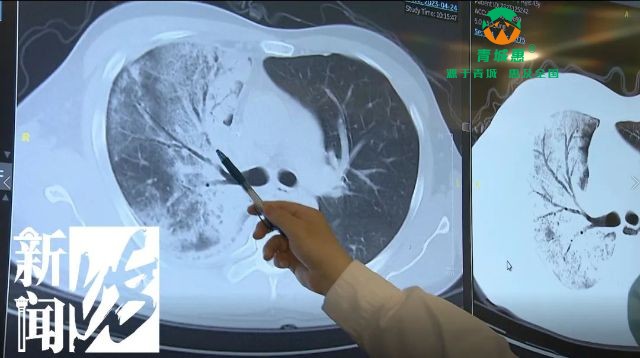

单肺严重感染,几乎丧失功能!已有孩子感染!病因竟是……

丹凤生活圈官方

05-08 10:15